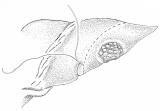

和綴じの方法を応用した、肝部分切除

和綴じの本をお持ちの方は、バラして見るのも一興かも。でも、ご先祖様が化けて出るかも